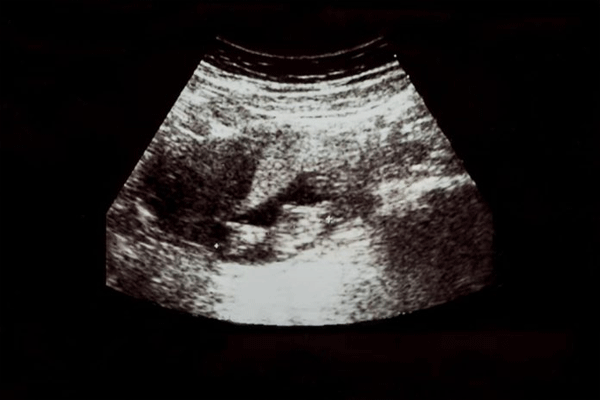

viral-news लग्नाला फक्त ३० दिवस झाले होते आणि मिनाक्षी (काल्पनिक नाव) काही दिवसांपासून वेगळे अनुभवत होती—जणू काही ती  गरोदर असण्याचे चिन्हे दिसत आहेत. तिने संशयाने डॉक्टरांकडे तपासणीसाठी भेट दिली. डॉक्टरांनी जबाबदारीपूर्वक केलेल्या अल्ट्रासाऊंडमध्ये गर्भ दीड महिन्यांची असल्याचे आढळले. मिनाक्षीला ऐकून धक्का बसला कारण तिची लग्नाची रात्र फक्त काही दिवसांपूर्वी झाली होती आणि त्यानंतरच तिने आपला पहिला शारीरिक संबंध ठेवले होते.

डॉक्टरांनी तिला सांगितले की, गर्भधारणेची आयु साधारणपणे अंतिम मासिक पाळीच्या पहिल्या दिवसापासून मोजली जाते, फक्त गर्भधारण झाल्यापासून नाही. त्यामुळे अल्ट्रासाऊंडमध्ये दिसणारी वयोमर्यादा खरी गर्भधारणेची तारीख दर्शवत नाही, तर अंतिम पाळीच्या दिवसापासून मोजलेली कालावधी असते. सामान्यतः अंडोत्सर्जन आणि गर्भधारण अंतिम पाळीपासून सुमारे दोन आठवड्यांनंतर होते, त्यामुळे अल्ट्रासाऊंडमध्ये गर्भाची वयोमर्यादा दीड महिन्यांची दिसली तरी प्रत्यक्ष गर्भधारण लग्नाच्या दिवशी किंवा त्यानंतर झाली असते. डॉक्टरांनी मिनाक्षीला हेही समजावून सांगितले की ही पद्धत शास्त्रीय दृष्ट्या योग्य आहे आणि यामुळे गर्भाचा विकास योग्य आहे का, प्रसूतीपूर्व तपासणी कधी करावी याची माहिती मिळते. viral-news मिनाक्षीची भीती दूर झाली आणि तिने विज्ञानाच्या या साध्या पण महत्त्वाच्या नियमाची कल्पना घेतली.